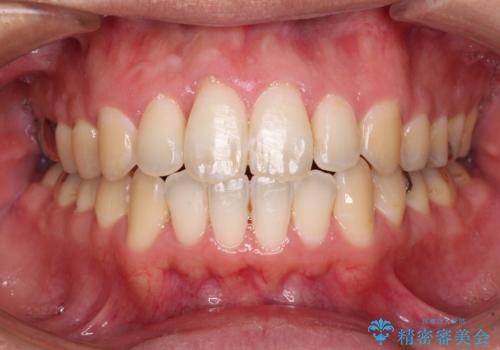

当初は奥歯のみの治療をご希望でしたが、話を進めていくうちに、軽度ではあるものの、幼少期の薬の影響で歯が変色していることがコンプレックスであるということが分かりました。

長年歯の色が塞ぎ込んでいた部分があるとのことで、これを機会に全ての歯を真っ白にするために、オールセラミッククラウンにて補綴治療を行うこととしました。

より白さが目立つように、自然な仕上がりではなく、作り物の雰囲気があるフルジルコニアクラウンにて補綴治療を行いました。